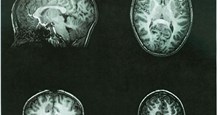

Cụ thể, nhóm nghiên cứu chỉ rõ, khi lưu lượng máu giảm đi ở khu vực Broca - một khu vực thùy trán của não sẽ khiến hệ thần kinh xử lý thông tin ngôn ngữ trở nên chậm, ngắt quãng và bị rối loạn tức thời. Chính vì vậy mà người thiếu máu trong vùng não Broca sẽ trở nên nói lắp.

Nghiên cứu còn phát hiện rằng, việc thiếu hụt lượng máu trong vùng não Broca diễn ra thường xuyên, mức độ nghiêm trọng hơn thì tần suất nói lắp của người đó cũng diễn ra nhiều hơn, nhanh hơn rất dễ nhận diện qua khẩu hình miệng, âm thanh ngôn ngữ phát ra.

Ngoài ra, không riêng gì cùng não Broca mà việc thiếu máu tới hệ thống truyền xung thần kinh nối liền ở phía trước và phía sau thùy thái dương (kết nối với vùng não Broca) cũng tham gia đóng góp vào việc nói lắp trên cơ thể người.